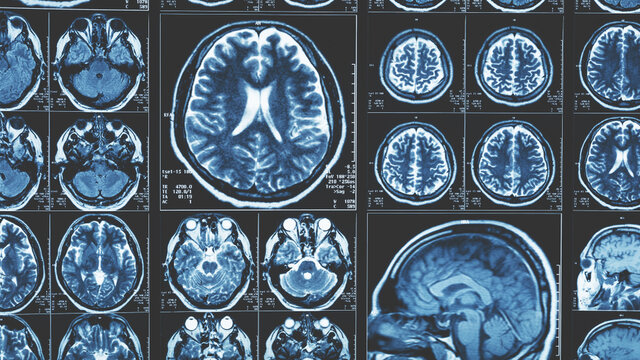

Historia de la Tomografía Computarizada

• Descubrimiento de los Rayos X

Descubrimiento de los Rayos X

El científico Wilhelm Conrad Röntgen descubre los rayos X, revolucionando la medicina al dar inicio a la radiología y al diagnóstico por imágenes